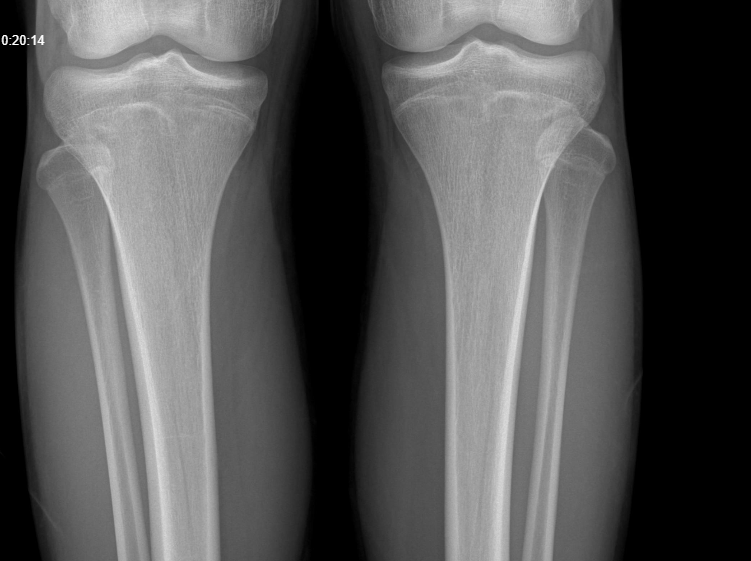

Do u have data on age of closure for those plates, thats more what im looking forUnfortunately I can't edit the post now, but its really unlikely that your femur & tibia plates are fused and your knees aren't, so I'd still use your knee xray over most things

won't do anything except give you brain damagegot a knee scan 2 months ago and my femur and tibia are partially fused at 18, should I spam AI?

by the way, if your knee plates are fused its very likely your wrists have aswell, spamming AI won't reopen ur platesgot a knee scan 2 months ago and my femur and tibia are partially fused at 18, should I spam AI?

I mean they aren’t exactly partially fused like the images you presented, they are a bit open. There’s a decent sized crack and not almost slim shut like those photos.by the way, if your knee plates are fused its very likely your wrists have aswell, spamming AI won't reopen ur plates

what letter would you assign them? do you have the pics on you? cause that would helpI mean they aren’t exactly partially fused like the images you presented, they are a bit open. There’s a decent sized crack and not almost slim shut like those photos.

but yes, getting knee xrays to determine your growth plate closure is a better option than a wrist xray, but its just a lot simpler to actually go ahead and get an xray of your wrists

This makes sense in theory but in reality doesn't apply, if your knees plates are fused then the chances of your spine and ankles somehow NOT being fused is very low / none, and even if they are not fused, they're 100% near fusion, meaning again, no significant height growth